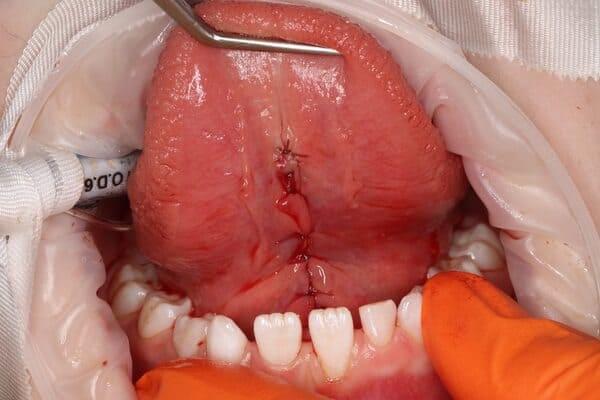

Корекція вуздечки. Бродик Богдан.

Пластика вуздечки язика — важлива процедура, яка забезпечує правильне формування дикції, а також формування зубощелепної системи. Вона сприяє коректному ортодонтичному лікуванню. В умовах анестезіологічного забезпечення протягом короткого часу було проведено пластику вуздечки язика, що дозволить у майбутньому гармонійно розвиватись щелепній системі.

Корекція вуздечки. Бродик Богдан.

Часто для отримання гарних ортодонтичних та логопедичних результатів без корекції вуздечки язика неможливо обійтись. У даному випадку ортодонтом була скерована пацієнтка шести років для того, аби провести відповідну корекцію. Після корекції вуздечки язика розпочато ортодонтичне лікування, яке в таких умовах дасть швидший та більш прогнозований результат.